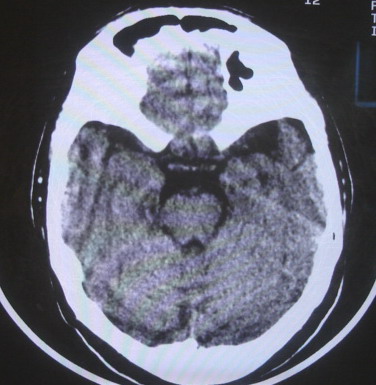

女  67岁 双下肢无力,行动不灵便

脑萎缩,腔隙性脑梗塞.

双侧额桥束及左侧脑室旁多发腔梗塞+老年性脑改变

多发腔梗、老年性脑改变、脑白质异常。